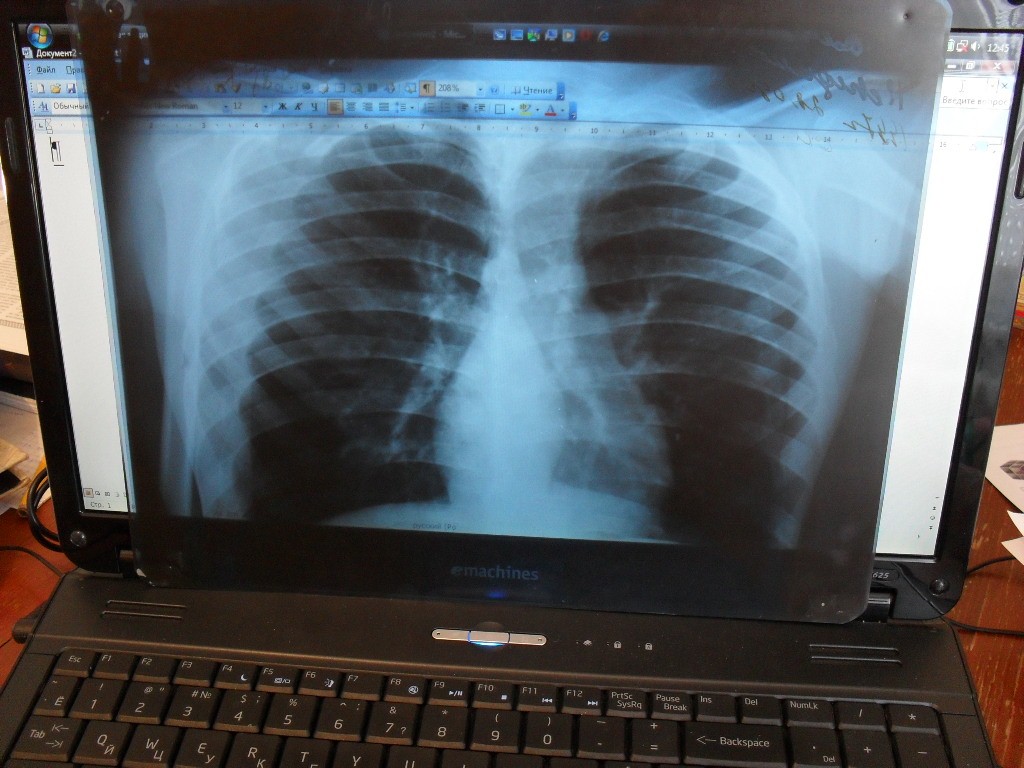

Для контроля над заболеваемостью взрослое население города должно ежегодно проходить обследование на флюорографе.